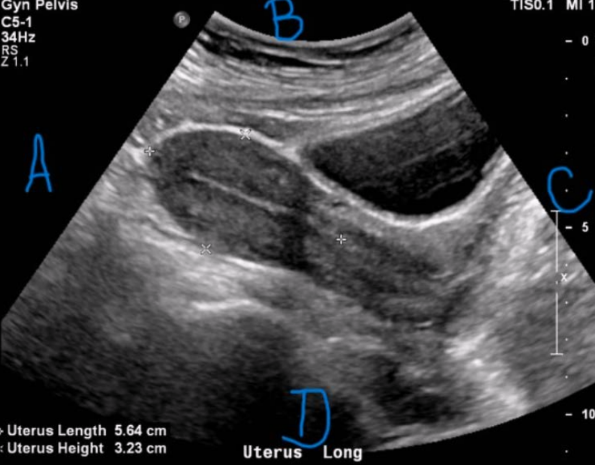

Is this image endovaginal or transabdominal?

a. Endovaginal

b. Transabdominal

Endovaginal

What is letter B in this image?

a. Superior

b. Right

c. Anterior

d. Posterior

Right

What is letter D in this image?

a. Anterior

b. Superior

c. Posterior

d. Inferior

Inferior